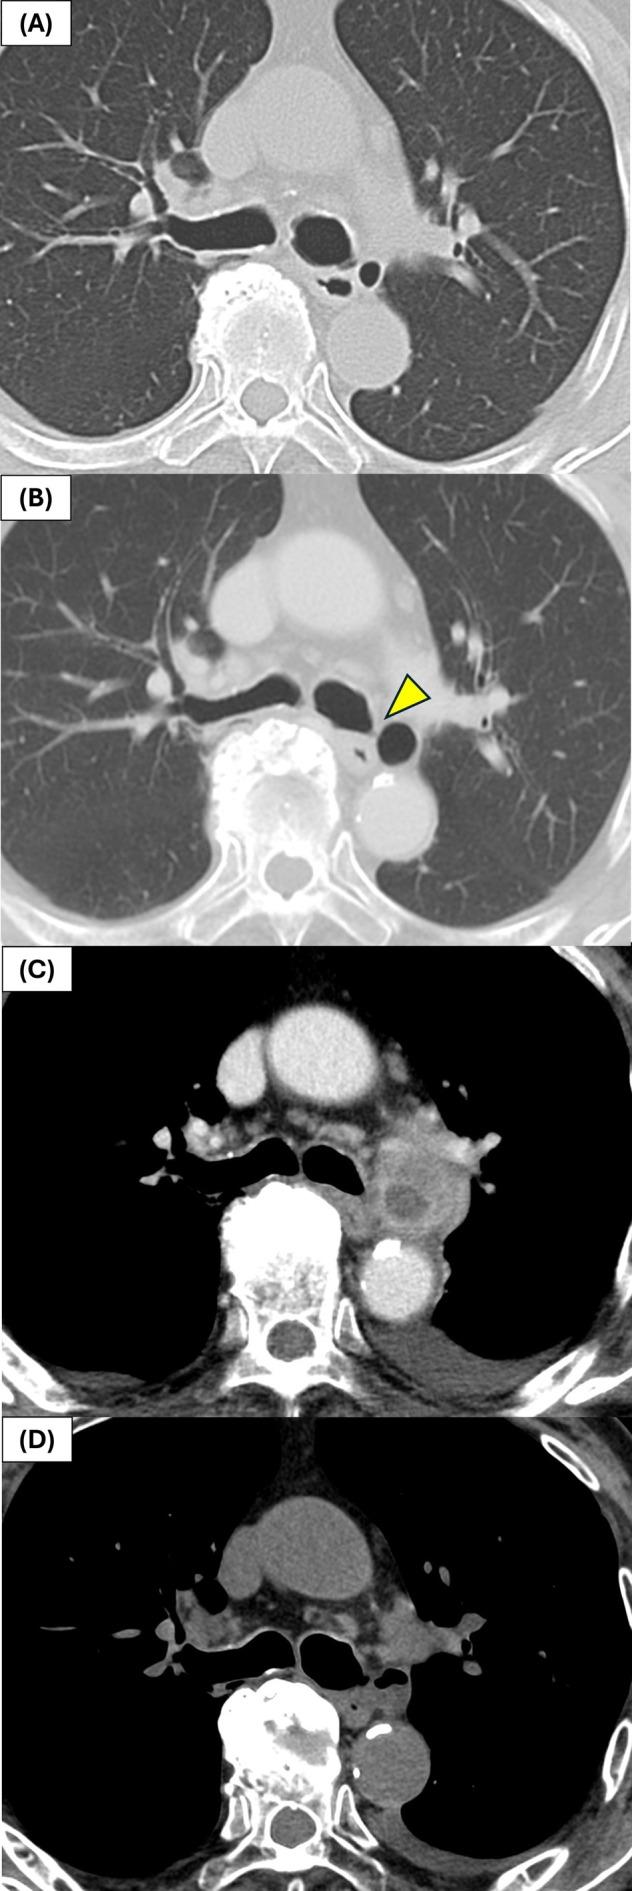

Bronchial diverticulum (BD) is a rare airway abnormality that rarely enlarges significantly or becomes infected. We report a case of an 80-year-old male with a 15-year history of asymptomatic BD that gradually increased in size and eventually developed into an abscess. Chest computed tomography revealed a cystic lesion adjacent to the left main bronchus with internal fluid and surrounding inflammation. Endobronchial ultrasound-guided transbronchial needle aspiration (EBUS-TBNA) enabled safe aspiration and identification of alpha-hemolytic despite the absence of a visible bronchial opening. The infection was successfully managed with antibiotics alone, thereby avoiding surgical intervention. This case highlights the potential for long-term asymptomatic BD to develop infection and demonstrates the diagnostic utility of EBUS-TBNA for lesions adjacent to vital structures. However, further studies are needed to clarify infection risk factors and optimal management strategies for BD.

摘要

支气管憩室(BD)是一种罕见的气道异常,很少会显著增大或发生感染。我们报告一例80岁男性,有无症状BD病史15年,其大小逐渐增加,最终发展为脓肿。胸部计算机断层扫描显示左主支气管旁有一个囊性病变,内部有液体且周围有炎症。尽管没有可见的支气管开口,但支气管内超声引导下经支气管针吸活检(EBUS-TBNA)实现了安全抽吸并鉴定出α溶血性菌。仅用抗生素就成功控制了感染,从而避免了手术干预。该病例突出了长期无症状BD发生感染的可能性,并证明了EBUS-TBNA对重要结构附近病变的诊断效用。然而,需要进一步研究以阐明BD的感染危险因素和最佳管理策略。